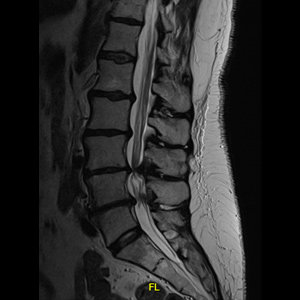

Spinal stenosis (Lumbar) Spinal stenosis (Cervical) Spinal stenosis (Thoracic) Lumbar Disc Herniation Spondylolisthesis Cervical Foraminal Stenosis Vertebroplasty Lumbar Fusion Anterior Cervical Fusion (ACDF) Posterior Cervical Fusion Thoracic Fusion Revision Lumbar Fusion Surgery Facet Joint Cyst Spinal Tumour Minimally Invasive Lumbar Fusion (XLIF) Minimally Invasive Lumbar Fusion (ALIF) Lumbar Fusion (TLIF) Thoraco-lumbar Fusion Lumbar Corpectomy Complex Lumbar Spine Surgery (Spino-pelvic fixation) Complex Cervical Spine Surgery Complex Thoracic Spine Surgery Occipito-cervical Fusion Minimally invasive surgery for thoracic disc herniation Other Related Topics